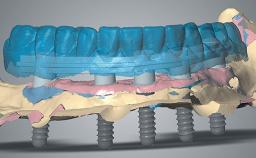

The author provides a step-by-step guide for meticulous planning and execution using a fully digital workflow. Of note, the maxillary rehabilitation was achieved in three phases using CAD/CAM technology: (1) PMMA provisional, fabricated prior to flapless guided implant placement and used to create the desired soft-tissue profile (2) PMMA definitive restoration prototype, used to confirm and perfect clinical details (3) Zirconia definitive restoration.